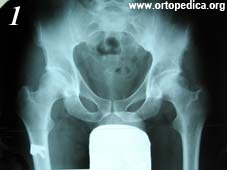

Пример №20 Ассептический некроз головки бедренной кости

1. До операции